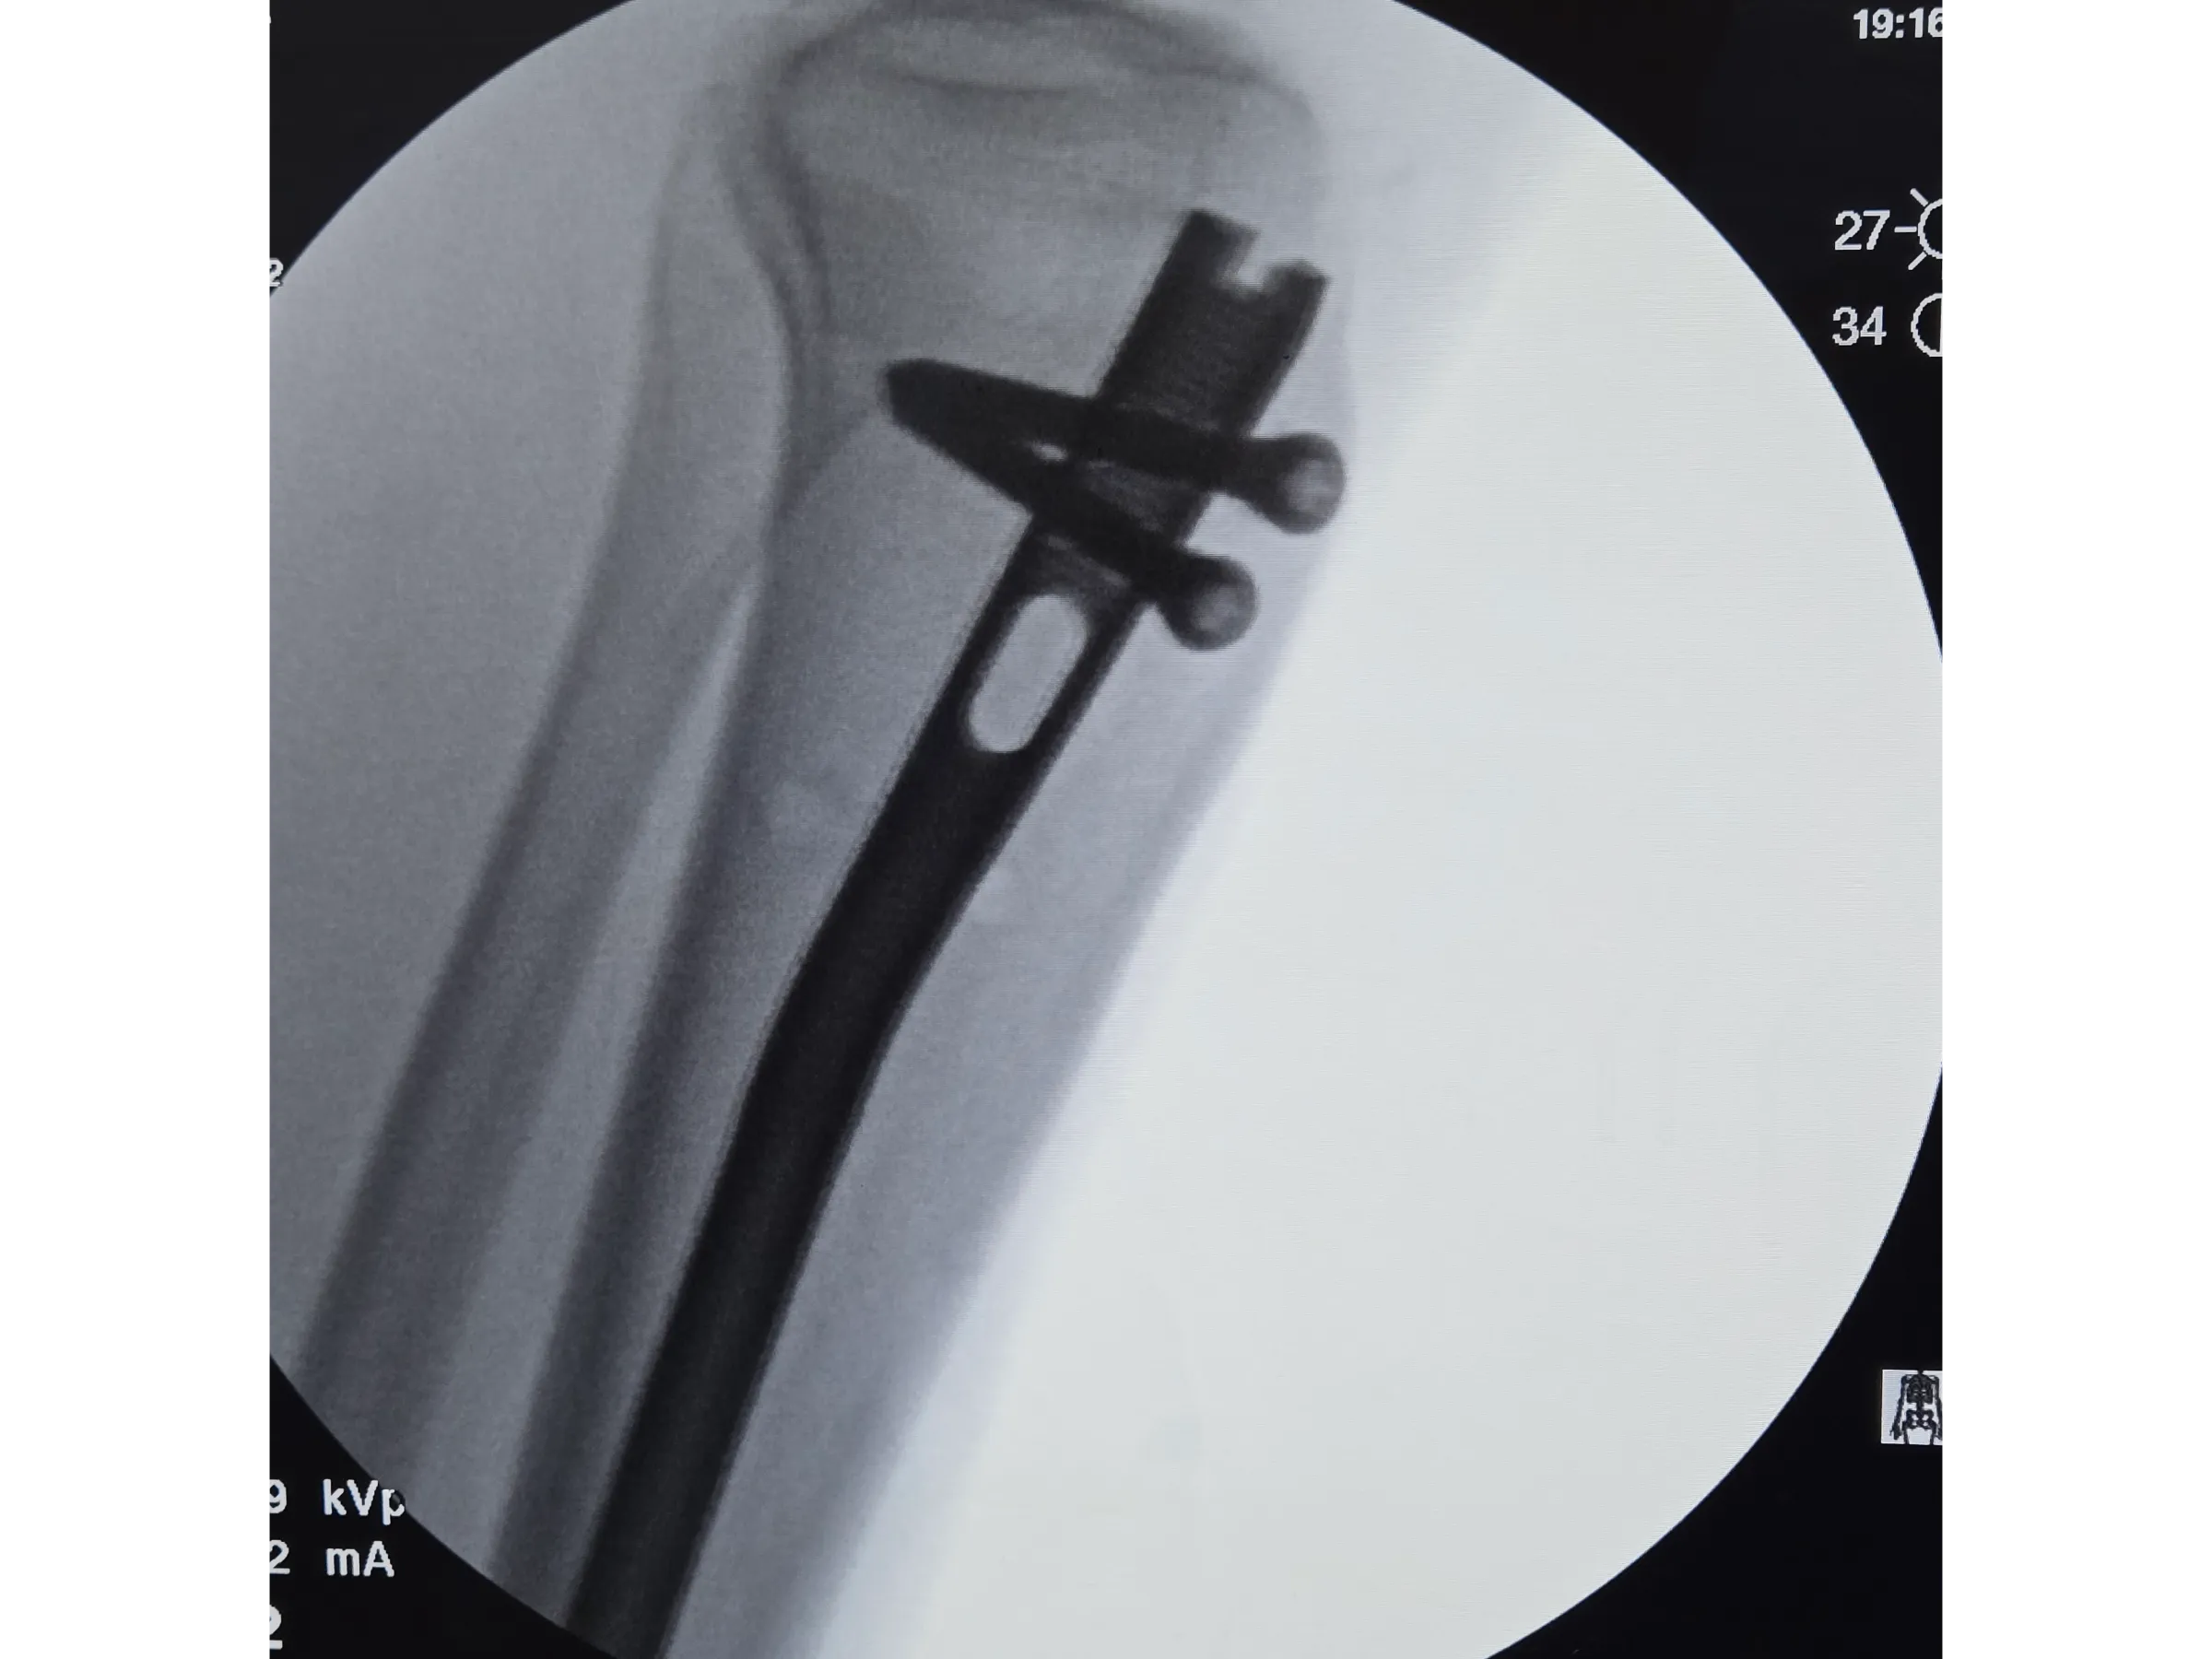

A estabilização de fraturas diafisárias da tíbia exige precisão no portal de entrada, alinhamento axial e proteção das partes moles. Este treinamento apresenta, de forma objetiva e prática, a técnica de implantação de haste intramedular por via infrapatelar, com demonstração detalhada dos passos cirúrgicos, controle radiográfico e execução minimamente invasiva sob perspectiva técnica.

- Inserção da haste intramedular e checagem do posicionamento;

- Bloqueios proximais e distais com abordagem minimamente invasiva;

- Bloqueios Proximais e Distais Minimamente Invasivos: Execução de bloqueios cruzados e distais com pequenos portais e controle por intensificador;